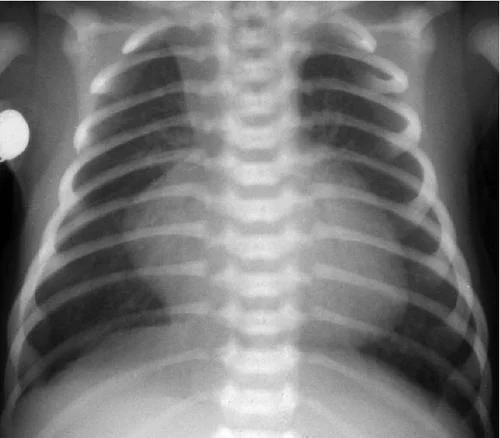

This is his CXR taken in Resus:

- What are the CXR findings?